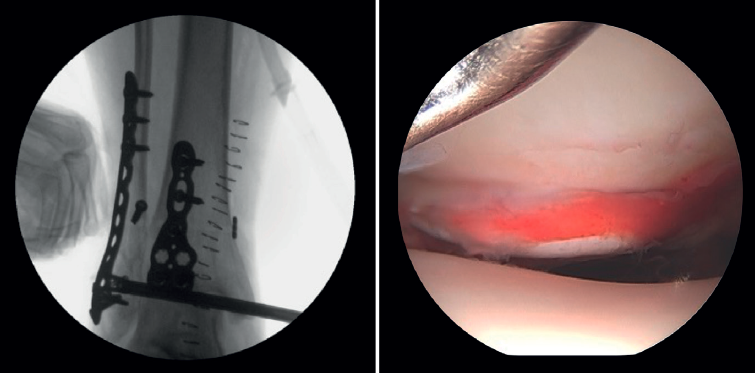

- Assessment of reduction of the posterior malleolus: arthroscopy can be used to verify reduction of the posterior malleolus(5)(Figure 2).

- Diagnosis of syndesmotic instability. Arthroscopy allows assessment of the integrity of the syndesmosis and the MCS on the radiograph and CT scan, especially in SER II and IV fractures. It has been shown that radiographic assessment is not always predictive of the syndesmotic lesion. In addition, arthroscopy ensures its anatomical reduction. Takao found that 87% (33/38) of the ankles with fractures had syndesmosis lesions detected by arthroscopy(20).

- Being able to visualize the malleolar incisura together with radioscopic control allows us to ensure correct positioning of the incisura fibularis, especially in patients with unstable injuries where there is a risk of malreduction due to shortening or rotation of the fibula(5,24).

- Arthroscopy can help avoid overcorrection of the syndesmosis, which is highly arthrogenic(5,24)(Figure 6).